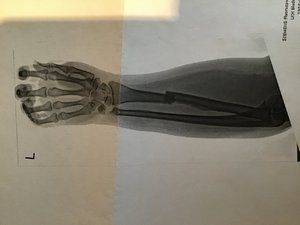

Am 12.10. habe ich mir bei einem Verkehrsunfall mit dem Fahrrad die Elle im linken Unterarm und ein Teil vom Handgelenk gebrochen.

Am 12.10. habe ich mir bei einem Verkehrsunfall mit dem Fahrrad die Elle im linken Unterarm und ein Teil vom Handgelenk gebrochen.

Die Bilder sind schon sehr krass.

Die Bilder sind schon sehr krass. Also etwa 12 Wochen nach dem Unfall. Ich werde aber sicher noch einige Physiotherapie Sitzungen in Anspruch nehmen bis die Beweglichkeit wieder voll da ist.

Also etwa 12 Wochen nach dem Unfall. Ich werde aber sicher noch einige Physiotherapie Sitzungen in Anspruch nehmen bis die Beweglichkeit wieder voll da ist.